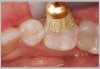

Figure 7